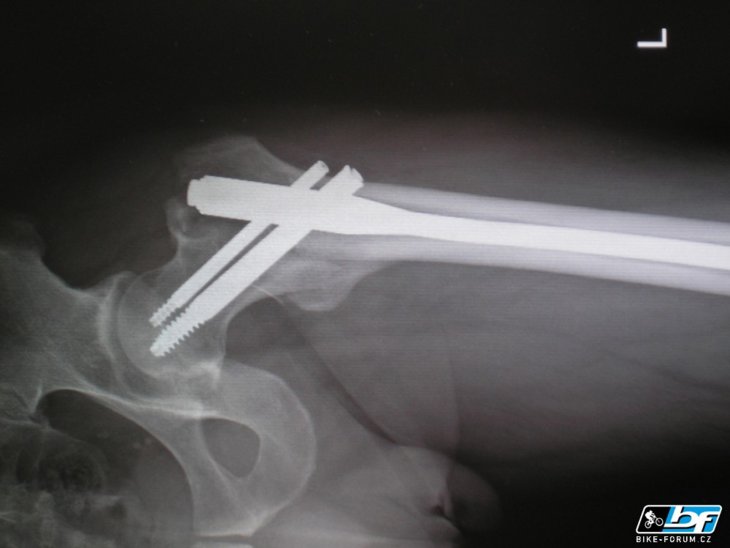

Náhradní kost

Je to titan !!

pačes:to není titan ale chirurgická ocel …i tak je to hoodně drahý

ten titan si nenech ve špitále vyndat, doma si z toho udělej něco na kolo:-)